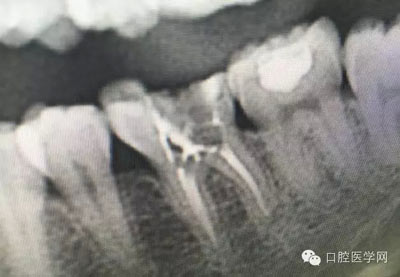

幾例根管再治療病例

根管治療,我們在大學的時候就學習的東西,標準就在那里放著,可是很多時候我們熟視無睹,放任我們的想象去做。我們多些重視,多些心思,會好很多,認真對待每顆牙齒。